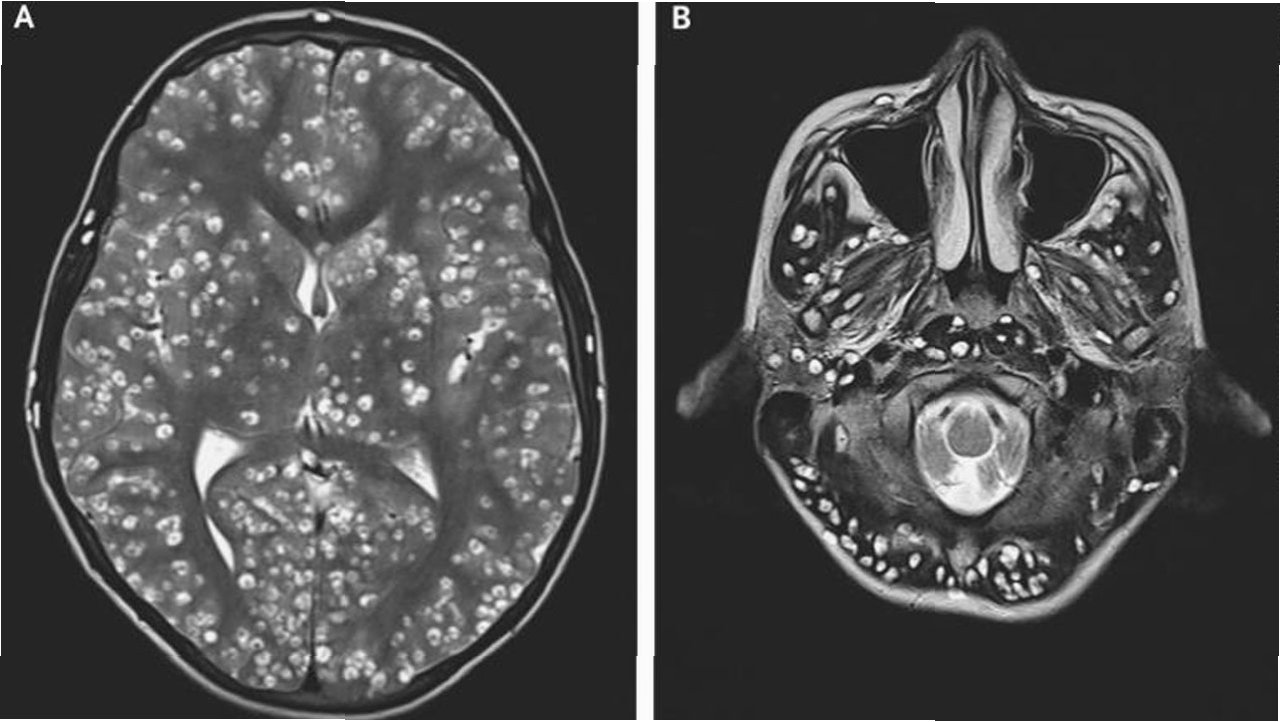

극심한 복통을 호소하며 병원으로 이송된 장씨는 검사 결과 기생충 감염으로 확진되었습니다. 의료진은 소화기관 손상과 함께 스파르가눔을 포함한 기생충이 체내에서 발견되었다고 밝혔습니다. 스파르가눔은 기생충 유충 단계를 의미하며, 이는 장씨가 겪은 고통의 원인이 되었습니다. 이 사건은 개인의 건강을 위해 과학적인 근거 없는 민간요법을 맹신하는 것이 얼마나 위험한지를 보여줍니다.

우중원 의사는 개구리 가죽을 몸에 붙이면 피부병이 낫는다는 소문은 근거가 없으며, 오히려 기생충이 인체에 침투하여 시력 저하, 두개강 내 감염, 생명까지 위협할 수 있다고 경고했습니다. 그는 건강에 대한 잘못된 정보가 얼마나 위험한 결과를 초래할 수 있는지 강조하며, 과학적인 근거를 바탕으로 건강 관리를 해야 한다고 조언했습니다. 전문가의 경고는 건강에 대한 올바른 정보를 습득하고, 검증되지 않은 민간요법에 의존하지 않도록 하는 데 중요합니다.